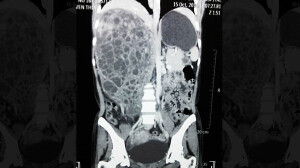

सायन म्हणजे लोकमान्य टिळक रुग्णालयातील डॉक्टरांनी एका वर्षापूर्वी काढलेल्या ट्यूमरची नोंद एका वर्षानंतर गिनीज बुक ऑफ वर्ल्ड रेकॉर्डमध्ये करण्यात आली आहे. हा ट्यूमर 5.5 किलो वजनाचा असल्यामुळे हा जगातील सर्वात मोठा ट्यूमर असल्याचं सायन रुग्णालयातील डॉक्टरांनी सांगितलं.

एका वर्षापूर्वी बिहारवरून आलेल्या महिलेच्या पोटातून हा ट्यूमर काढण्यात आला होता. या महिलेचं ऑपरेशन 2016 च्या नोव्हेंबर महिन्यात करण्यात आलं होतं. महिलेला वाटलं आपल्याला दिवस गेल्यामुळे पोट मोठं दिसतंय. त्यामुळे आधी तिने जास्त लक्ष दिलं नाही. पण, नंतर तिची प्रकृती बिघडली. तिच्यावर बिहारमध्येही उपचार सुरू होते. शेवटी, ऑपरेशन शिवाय दुसरा पर्याय डॉक्टरांकडे नव्हता.

ट्यूमरमुळे या महिलेला भूक लागत नव्हती. त्यामुळे शरीरातील रक्त कमी झालं होतं. तिच्यावर 2 ते 3 आठवडे निरीक्षणाखाली ठेवलं गेलं. पण, शेवटी ऑपरेशन करण्याचा निर्णय घेतला गेला. त्यानंतर शस्त्रक्रिया करुन ट्यूमर काढण्यात आला.

या ट्यूमरचा आकार आम्हाला माहीत नव्हता. पण, तो जेव्हा काढला, तेव्हा कळलं की त्याचं वजन 5.5 किलो आहे. आम्हाला भीती देखील होती की पेशंट वाचू शकेल की नाही. गिनीज बुकसाठी आम्ही नोंदणी केली होती. पण, त्यानंतर सर्व तपासणी वेगैरे करण्यात 6 ते 7 महिने गेले. त्यानंतर आता गिनीज बुक ऑफ वर्ल्ड रेकॉर्डमध्ये नोंद करण्यात आली आहे.